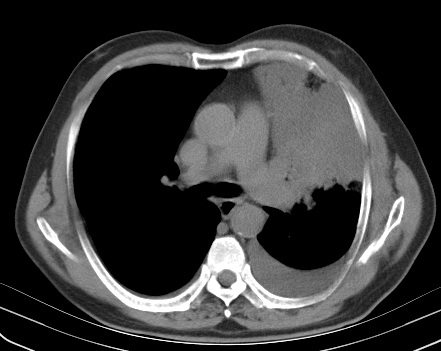

以下是引用老爱克斯新网客在2008-7-31 6:30:00的发言:[br]左肺上叶大片状病灶,左肺上叶支气管狭窄呈鼠尾状,左肺门增大,纵隔内见肿大淋巴结,左侧胸腔积液,余肺清晰。左肺中心型肺癌淋巴结转移,

以下是引用zjb在2008-7-31 6:32:00的发言:[br]左侧中心性肺癌 阻塞性肺炎 肺不张 胸腔积液 建议气管镜

以下是引用zjzjr在2008-7-31 8:45:00的发言:[br]考虑左侧中心性肺癌伴阻塞性肺炎,左肺上叶肺不张,纵隔淋巴结转移;左侧胸腔积液。建议行纤支镜检查。

以下是引用sdzyy在2008-7-31 8:47:00的发言:[br]病灶较治疗前有所进展,胸水增多, 左侧中心性肺癌 并 阻塞性肺炎 肺不张 胸腔积液 可能性大; 建议气管镜检查。 [br] [br]